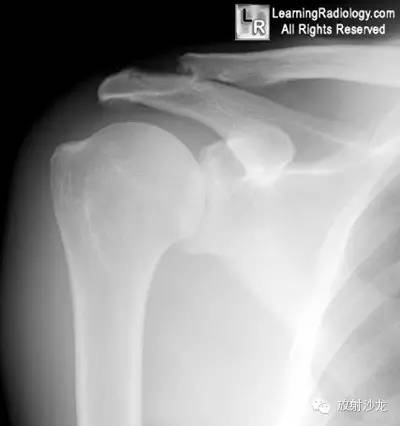

锁骨远端骨质溶解1例X线影像表现

29岁男性,举重员,肩关节疼痛 医学百科网 | YxBaike.Com

右肩关节—中立位

2.锁骨远端骨质吸收 医学百科网 | YxBaike.Com

3.锁骨远端骨量减少 医学百科网 | YxBaike.Com

4.关节周围肿胀 医学百科网 | YxBaike.Com

5.关节周围囊样骨质侵蚀 医学百科网 | YxBaike.Com

锁骨远端骨质溶解: 医学百科网 | YxBaike.Com

年轻举重员,可见锁骨远端骨质吸收及小囊样改变,该区域疼痛数月(白箭头)。